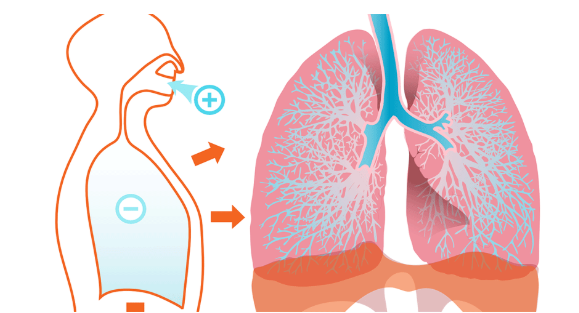

肺是人体最重要的器官,最重要的功能是攸关生命的呼吸。现在的生活环境空气品质普遍不佳,像是汽机车废气、PM2.5、燃烧东西的烟等,这些空气污染物都会刺激肺部,会影响肺部换气、使得肺功能下降。

肺

虽然我们可能难以避免这些空气污染物,但可以从自己做得到的方面来保养肺部,像是出门时配戴口罩、多运动提升体能等。另外平常也可以吃一些有助肺部健康的食物,《heho健康》介绍营养师推荐的6种食物,帮助补充身体热量与体力,部分的营养素能提高体内抗氧化、抗发炎能力,让肺部在受到感染之前就有比较好的免疫力。